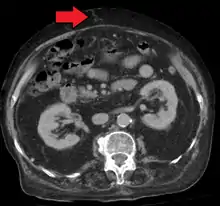

In addition, a widened (dilated) portal vein as seen on a CT scan or MRI may raise the suspicion about portal hypertension. A cutoff value of 13 mm is widely used in this regard, but the diameter is often larger than this is in normal individuals as well.[9]

Ultrasonography (US) is the first-line imaging technique for the diagnosis and follow-up of portal hypertension because it is non-invasive, low-cost and can be performed on-site.[17]

A dilated portal vein (diameter of greater than 13 or 15 mm) is a sign of portal hypertension, with a sensitivity estimated at 12.5% or 40%.[18] On Doppler ultrasonography, a slow velocity of <16 cm/s in addition to dilatation in the main portal vein are diagnostic of portal hypertension.[19] Other signs of portal hypertension on ultrasound include a portal flow mean velocity of less than 12 cm/s, porto–systemic collateral veins (patent paraumbilical vein, spleno–renal collaterals and dilated left and short gastric veins), splenomegaly and signs of cirrhosis (including nodularity of the liver surface).[17]

The hepatic venous pressure gradient (HVPG) measurement has been accepted as the gold standard for assessing the severity of portal hypertension. Portal hypertension is defined as HVPG greater than or equal to 5 mmHg and is considered to be clinically significant when HVPG exceeds 10 to 12 mmHg.[20]